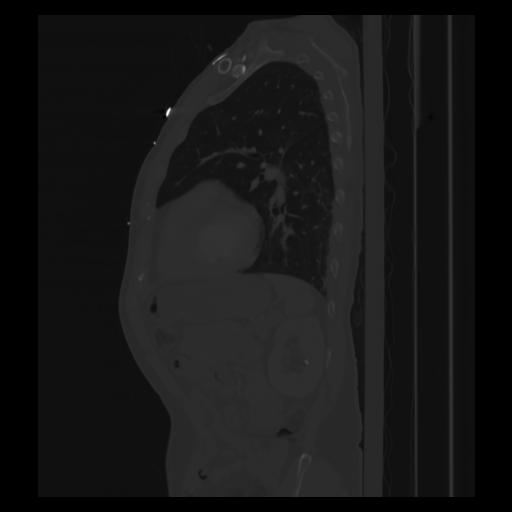

30 CUERPO,CE,Sagittal,3.000,CUERPO,Sagittal,